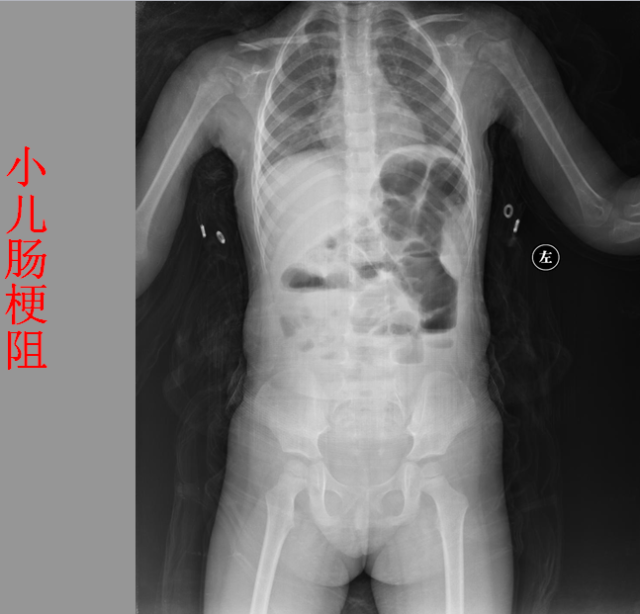

05